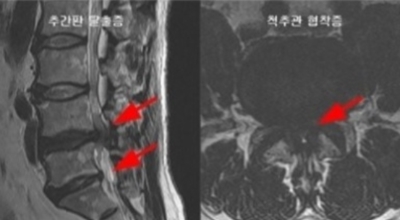

정상인 사람은 척추가 완만히 휘어져 있는데 척추관 협착증인 사람은 더 일자로 펴져 있고 정상인 사람의 척추관은 공간이 적당한데 비해 척추관척 협착증인 사람은 척추관이 일그러져 있어요. 척추관 협착증 환자는 자기 공명 영상(MRI)에서 보면 척추관 내 신경을 싸고 있는 경막 안에 정상에서 보이던 뇌척수액이 보이지 않는다는 특징이 있어요.

가장 가장 유명한 구별법은 허리를 앞으로 굽혀보는 것으로 허리디스크일 경우 더 통증이 심해지지만 척추관 협착증일 경우 신경의 압박이 완화되어 통증이 완화되거나 사라지는 것을 경험할 수 있겠습니다. 또 허리디스크 환자는 누워서 두 다리를 들어올릴 수 없지만 척추관 협착증 환자는 누워서 두 다리를 들어올릴 수 있다고 합니다. 이런식으로 누구나 간단히 구별할 수 있겠습니다.